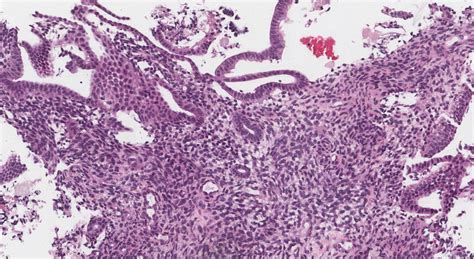

Photomicrographs of the endometrium in the proliferative phase (a, b